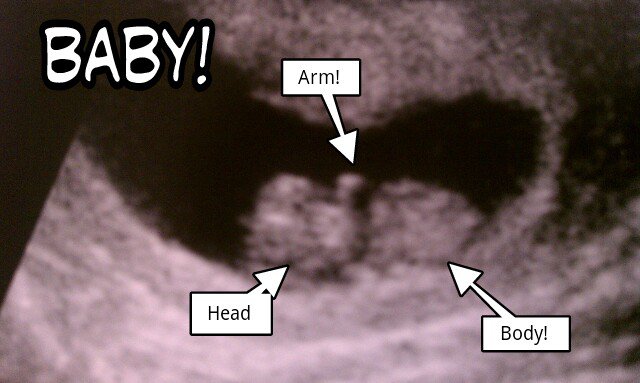

We were very involved with the actual pregnancy for both our kids. We attended check ups at the OB clinic and did classes, just like any new parents would do. We got to participate in ultrasounds and have access to our doctor for questions and concerns, just like any new parents.